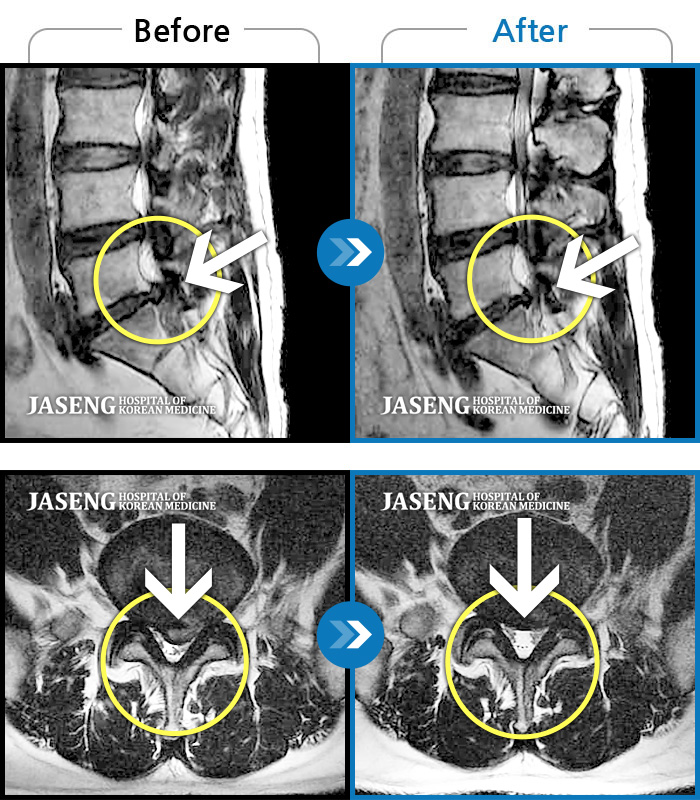

허리디스크

잠실 · 한상욱 원장

우측 엉치부터 우측 다리부터 발끝까지 저리고 아프다. 감각까지 먹먹하다.

촬영시기

2022.04.15 ~ 2022.10.22

2022.12.02